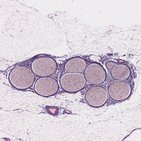

Le plexus sacré est un réseau de nerfs composé des rameaux antérieurs des nerfs spinaux L4-L5 (tronc lombo-sacré) et des nerfs spinaux S1-S4 qui sortent de la colonne vertébrale soit par les deux derniers foramens intervertébraux soit par les foramens sacrés antérieurs. Le plexus est situé antérieurement à l'artère et à la veine iliaque interne et antérieurement au muscle piriforme.